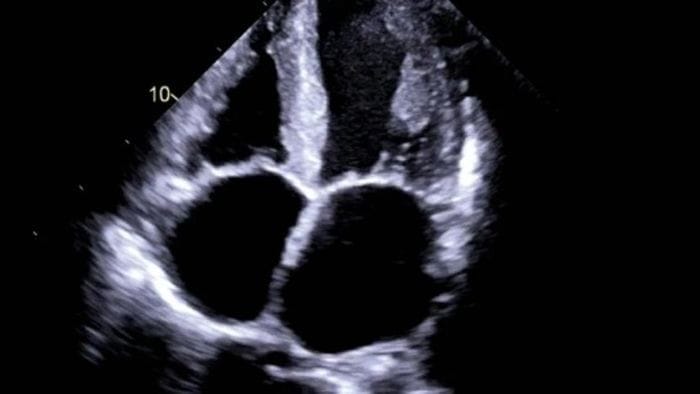

L’amidollosi cardiaca è una condizione caratterizzata da un eccesso di proteine nel cuore, che può compromettere l’elasticità muscolare. Grazie alle tecniche di imaging cardiologico avanzato, è possibile ottenere diagnosi più rapide e precise. L’ambulatorio del «Papa Giovanni» si dedica alla valutazione di questa patologia, offrendo un supporto specializzato per individuare e gestire tempestivamente eventuali alterazioni del muscolo cardiaco.

AMIDOLLOSI CARDIACA. Con le tecniche di imaging cardiologico avanzato diagnosi più tempestive. Il ruolo dell’ambulatorio del «Papa Giovanni». 🔗 Leggi su Ecodibergamo.it